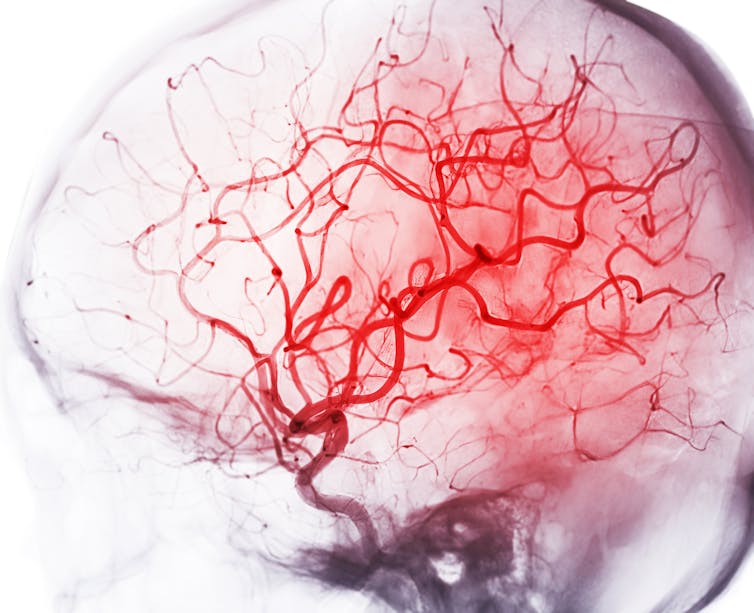

Luckily, the brain leaves behind evidence of its energy use through the pattern of the vessels that distribute blood throughout it. I figured I could look at the density of capillaries – the thin, one-cell-wide vessels that transfer gases, glucose and metabolites between brain and blood. These capillary networks would be preserved in the brains in my freezers.

A demand-based brain should be comparable to a road system. If arteries and veins are the major highways that carry goods to the town of specific parts of the brain, capillaries are akin to the neighborhood streets that actually deliver goods to their final users: individual neurons and the cells that work with them. Streets and highways are built on demand, and a road map shows what a demand-based system looks like: Roads are often concentrated in parts of the country where there are more people – the energy-guzzling units of society.

In contrast, a supply-limited brain should look like the river beds of a country, which couldn’t care less about where people are located. Water will flow where it can, and cities just have to adjust and make do with what they can get. Chances are, cities will form in the vicinity of the main arteries – but absent major, purposeful remodeling, their growth and activities are limited by how much water is available.

Would I find that capillaries are concentrated in parts of the brain with more neurons and supposedly require more energy, like streets and highways built in a demand-based manner? Or would I find that they are more like creeks and streams that permeate the land where they can, oblivious to where the most people are, in a supply-driven manner?

What I found was clear evidence for the latter. For both mice and rats, capillary density makes up a meager 2% to 4% of brain volume, regardless of how many neurons or synapses are present. Blood flows in the brain like water down rivers: where it can, not where it is needed.